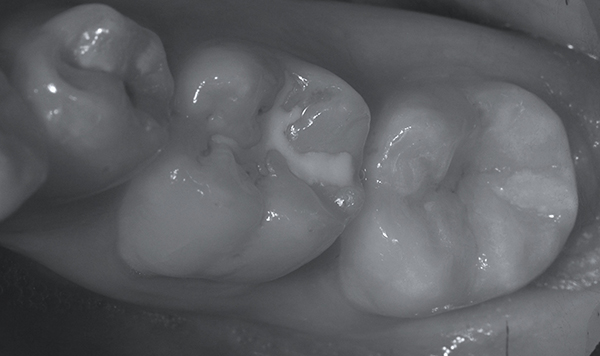

Il Case-Report in questione descrive il trattamento di una giovane paziente che si presenta all'osservazione clinica a causa del disfacimento superficiale della superficie masticatoria del secondo molare inferiore di destra. ( 4.7 )

La peculiarità di questo caso clinico risiede nel fatto che l'amelogenesi imperfetta ha interessato un solo elemento dentale del cavo orale e solo parzialmente lo spessore dello smalto del dente in questione.

All'anamnesi dentale la paziente riferisce che l'elemento dentale in posizione 4.7 si è sempre presentato, rispetto agli altri elementi dentali dei settori posteriori, di colore più scuro tendente al brunastro ma che comunque aveva mantenuto, sostanzialmente, nel tempo le proprie caratteristiche anatomiche e la funzione masticatoria originale.

All'esame obiettivo, l'elemento dentale in questione presenta un'abbondante perdita di sostanza dentale interessante quasi interamente la superficie occlusale e vestibolare ed evidenzia un colore marrone-brunastro nelle parti profonde disgregate mentre un aspetto di smalto normale nella porzione mesiale del dente.

La consistenza al sondaggio di tale tessuto alterato nella colorazione appare dura e non sono presenti segni di rammollimento dovuto all'instaurarsi di patologia cariosa ma piuttosto un progressivo sfaldamento dovuto a distacchi coesivi di porzioni di smalto affetto da amelogenesi imperfetta congenita.

La patologia non ha interessato in toto tutto lo smalto dell'elemento dentario.